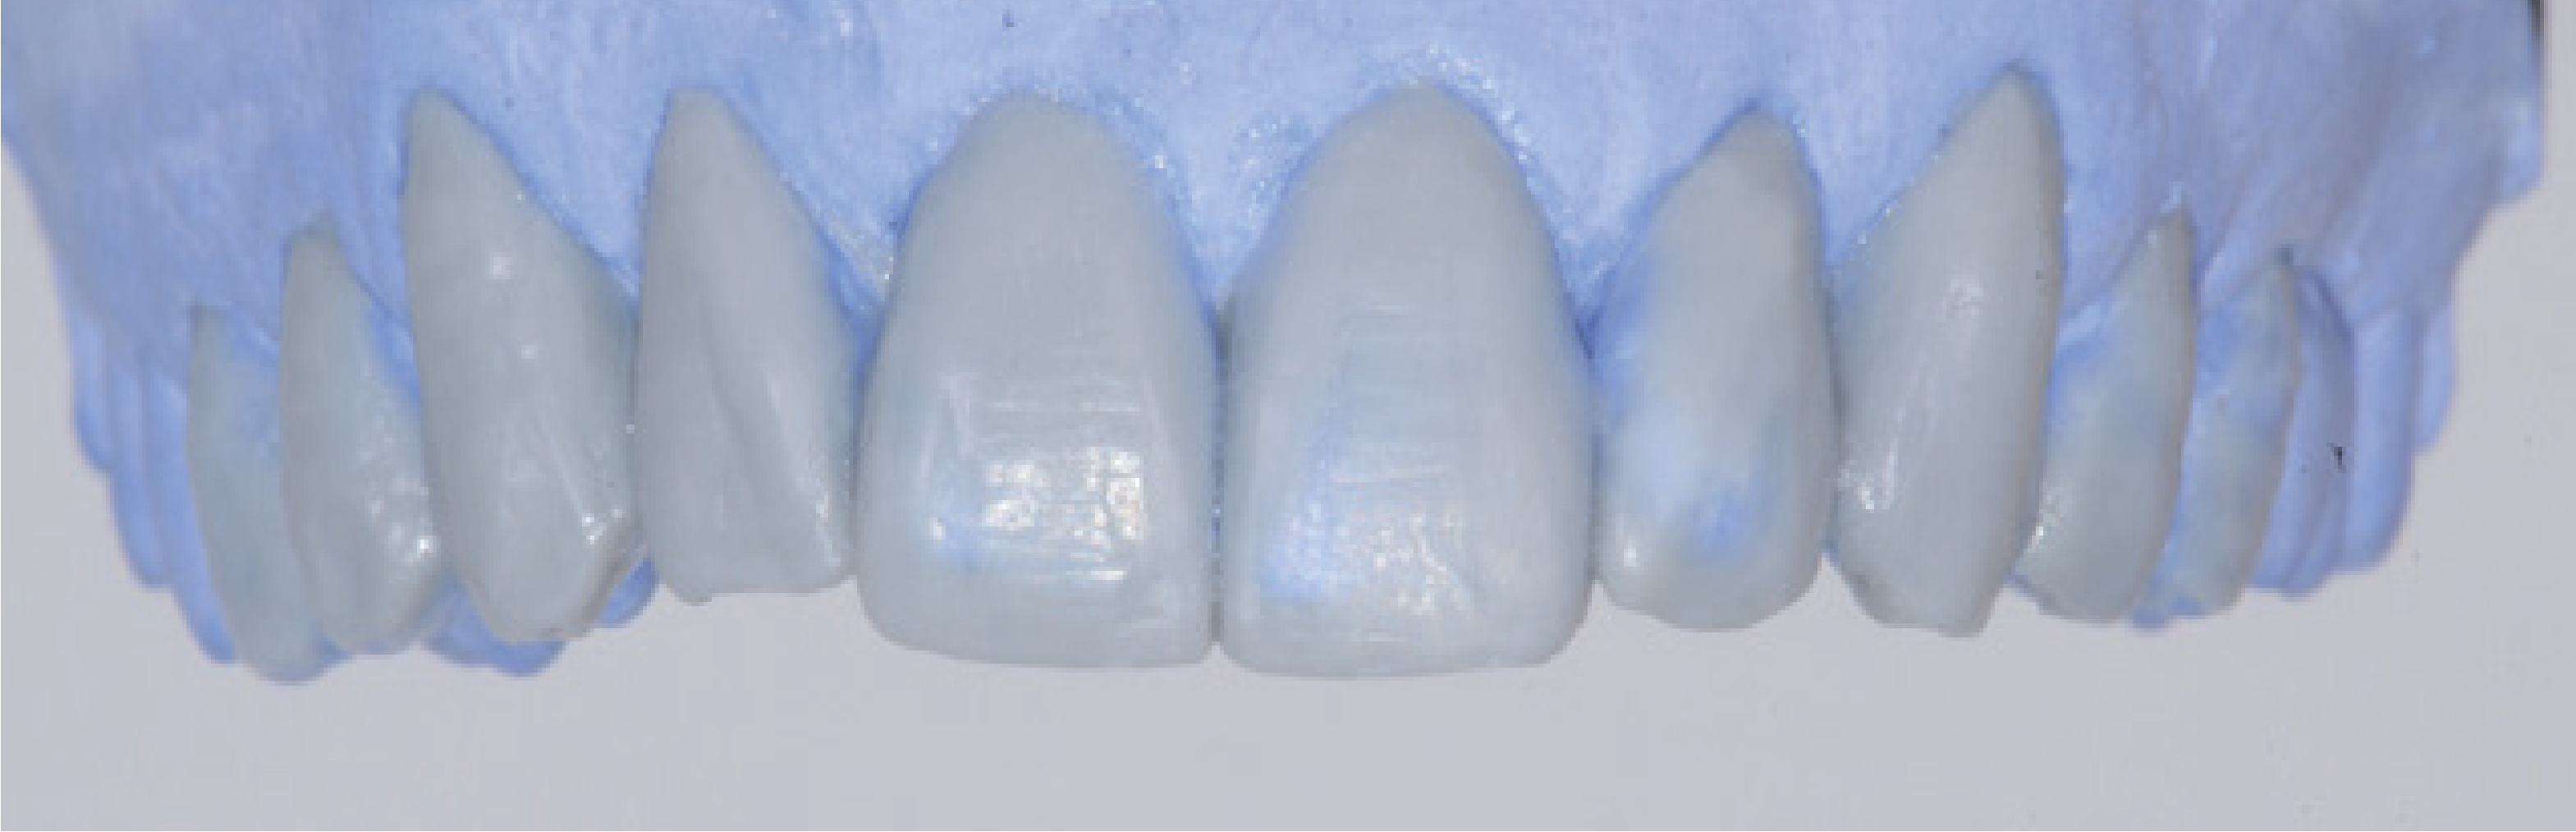

Використовуючи необхідну інформацію, відображену на mock-up, який був змодельований у ротовій порожнині, технік зробив wax-up ідеального результату естетичного лікування (мал. 5).

Він переніс особливості реконструкції естетичної зони безпосередньо з прямого mock-up - в напрямку від верхнього правого другого премоляра до верхнього лівого другого премоляра, заповнюючи «щоковий коридор». Осьовий напрямок ікла змоделювали за допомогою артикулятора, щоб виконати дизоклюзію задніх зубів у разі динамічної оклюзії з вирівняними нижніми зубами. Такий фізіологічний орієнтир дозволяє уникнути впливу неконтрольованих зусиль у зоні моляра і забезпечує довготривалість реконструкції. З доведеного до ідеального стану wax-up на моделі зробили три силіконові відбитки.